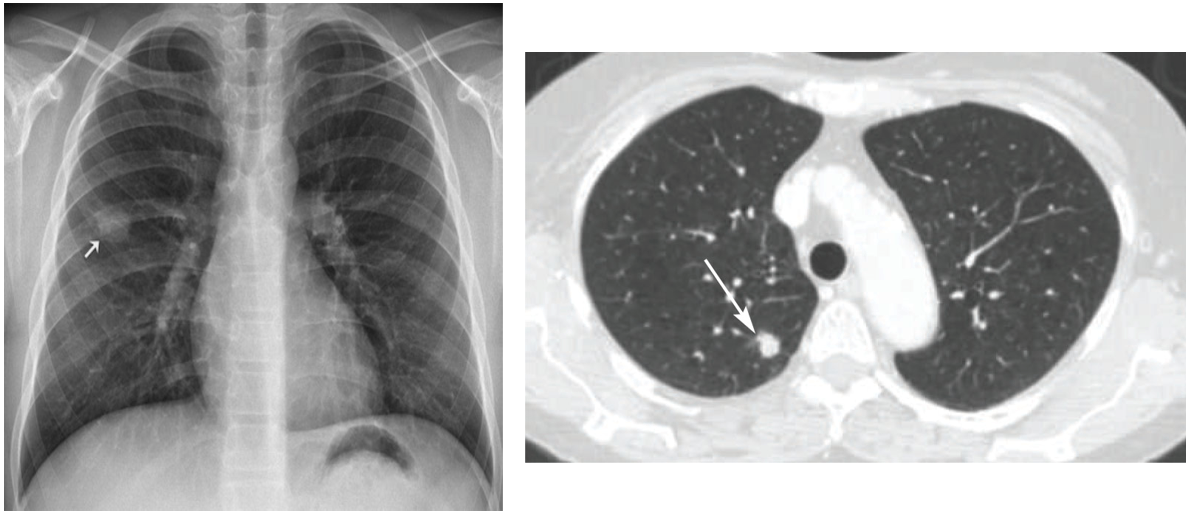

1) CXR

(1) Mass, nodule: m/c

* CXR에서 mass-like lesion이 있을 때 반드시 폐암, 폐결핵, 폐농양을 감별해야 한다.

(2) GGO, cyst, cavitation

(3) 무기폐(atelectasis): Golden S sign (RUL atelectasis + central airway mass), Luftsichel sign (LUL atelectasis + central airway mass) 등

(4) 흉막 삼출(pleural effusion): 악성 흉수나 lymphatic obstruction의 경우 발생

1) 정의: CXR/CT상 주위의 정상 폐실질과 분명한 경계를 나타내는 1~6cm 크기의 단일 음영

2) 분류

(2) Solid 양상에 따른 분류: Solid, sub-solid, ground-glass로 구분

• 폐실질이 잘 보이는 lung window에서 평가